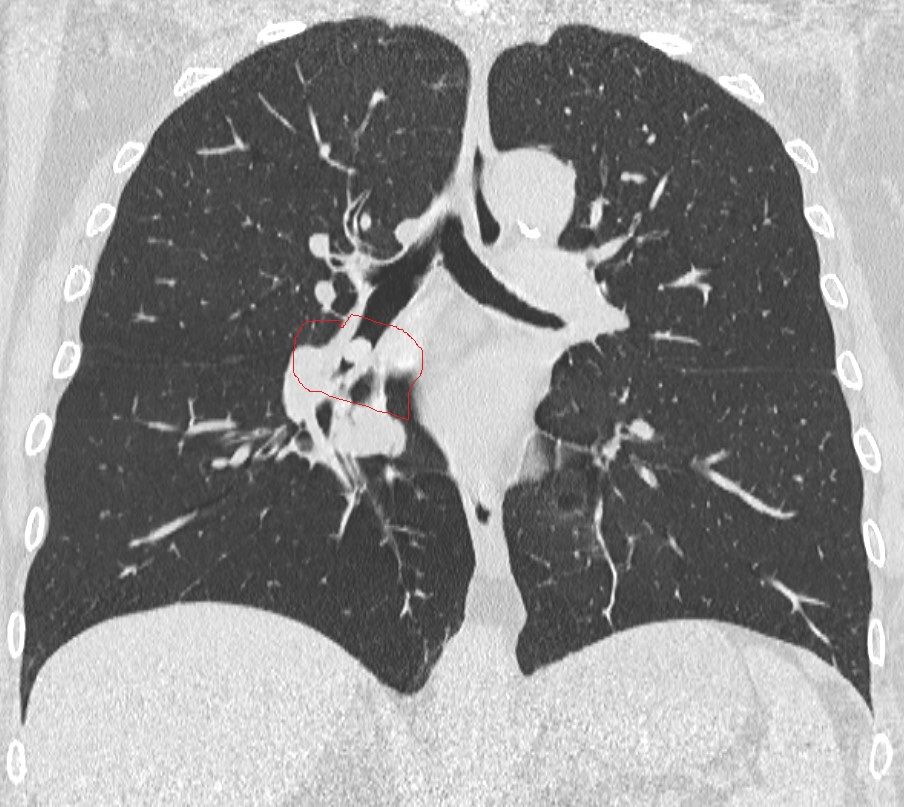

La donna, giunta al Pronto Soccorso con sintomi respiratori ad insorgenza acuta, insorti durante il pranzo, era stata rapidamente presa in carico dal personale dell’Emergenza-Urgenza e sottoposta dalla radiologa di turno, dott.ssa Chiara Ragone, ad esami radiologici, tra cui una TAC toracica. Da tali esami è emersa un’ostruzione subtotale del bronco inferiore del polmone destro causata da sospetto corpo estraneo.

Prontamente trasferita in sala di Endoscopia Toracica, la paziente è stata sottoposta ad anestesia locale e, tramite videobroncoscopio flessibile, utilizzando una specifica pinza a cestello, le è stato rimosso il corpo estraneo, che è risultato essere un seme di cece che, inalato nelle vie aeree e che si era andato a conficcare nel bronco inferiore del polmone destro della donna, ostruendolo totalmente.